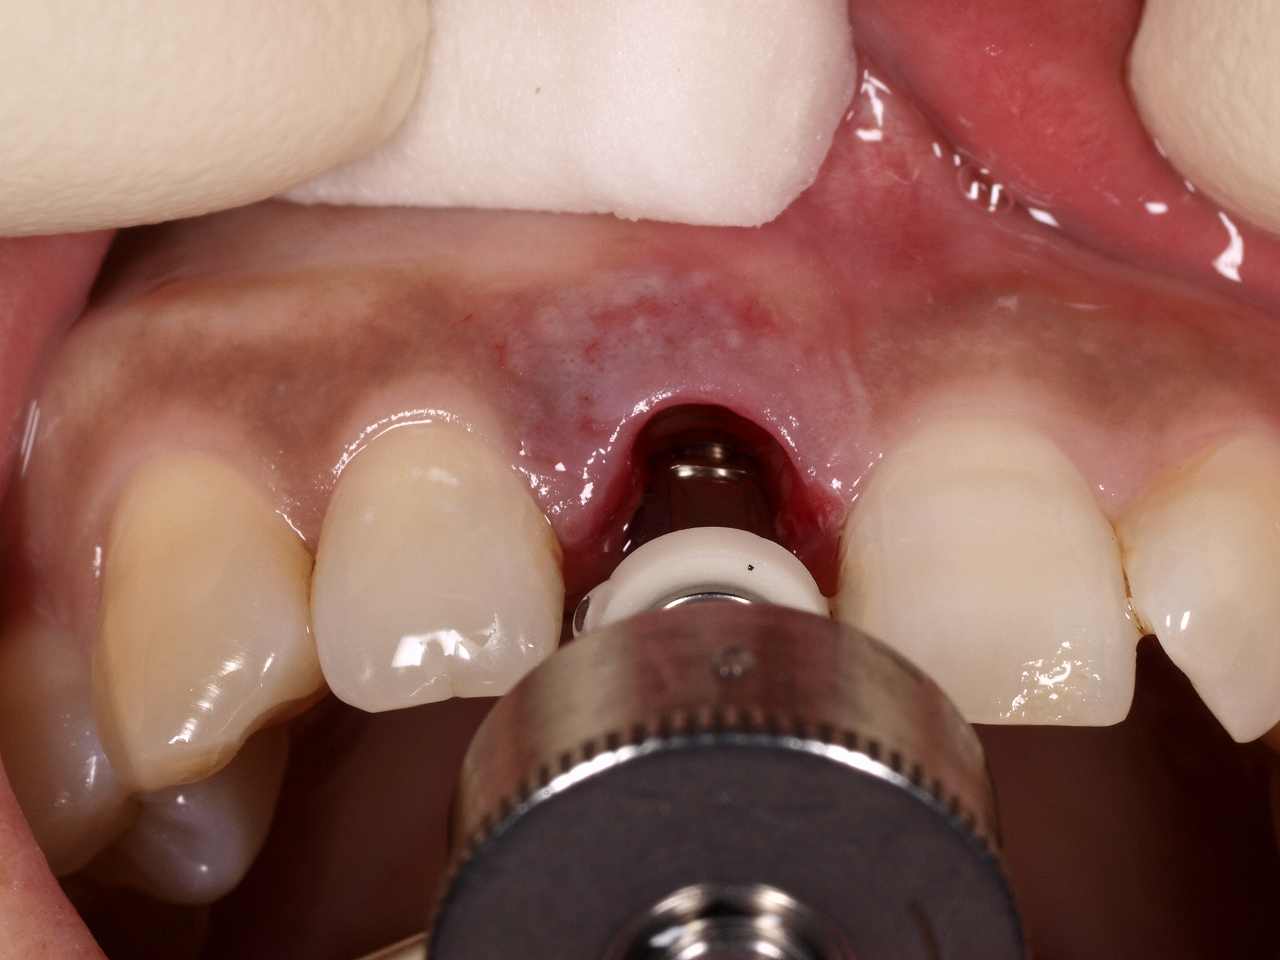

インプラント窩を形成

インプラント埋入後、仮歯をひときわ短いレスカンツゥアーのはを入れて終了